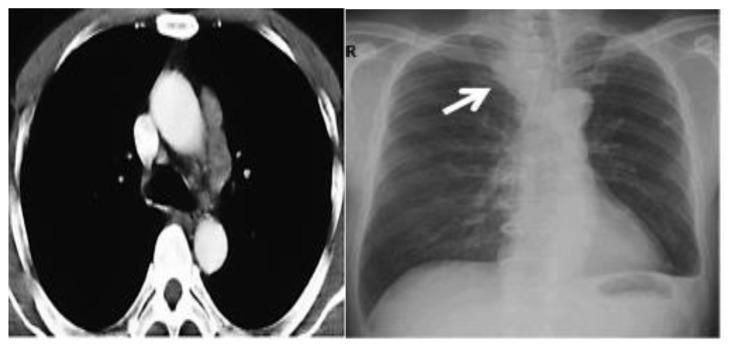

As less invasive options for surgical tumor removal, minimally invasive ablative techniques have gained popularity. Several solid tumors are being treated with cryoablation, a non-heat-based ablation technique. Cryoablation data in comparison over time demonstrates better tumor response and faster recovery. Combining cryosurgery with other cancer therapies has been explored to improve the cancer-killing process. Cryoablation with the combination of immunotherapy, results in a robust and efficient attack on the cancer cells. This article focuses on investigating the ability of cryosurgery to create a strong antitumor response when combined with immunologic agents resulting in a synergetic effect. To achieve this objective, we combined cryosurgery with immunotherapy using Nivolumab and lpilimumab. Five clinical cases of lymph node, lung cancer, bone, and lung metastasis were followed and analyzed. In this series of patients, percutaneous cryoablation and addressing immunity agents were technically feasible. In the follow-ups, there appeared to be no radiological evidence of new tumor development.

作为手术肿瘤切除的微创选择,微创消融技术已经越来越受欢迎。几种实体肿瘤正在接受冷冻消融治疗,这是一种非热消融技术。随着时间的推移,冷冻消融的数据显示出更好的肿瘤反应和更快的恢复。冷冻手术与其他癌症治疗方法的结合已被探索用于改善癌症杀伤过程。冷冻消融联合免疫疗法可以有效地攻击癌细胞。本文重点研究了冷冻手术与免疫药物联合使用时对肿瘤产生强烈抗肿瘤反应的能力,从而产生协同作用。为了实现这一目标,我们使用 Nivolumab 和 ipilimumab 将冷冻手术与免疫疗法相结合。对 5 例淋巴结、肺癌、骨和肺转移的临床病例进行了随访和分析。在这一系列患者中,经皮冷冻消融和免疫治疗具有技术可行性。在随访中,似乎没有新的肿瘤发展的放射学证据。